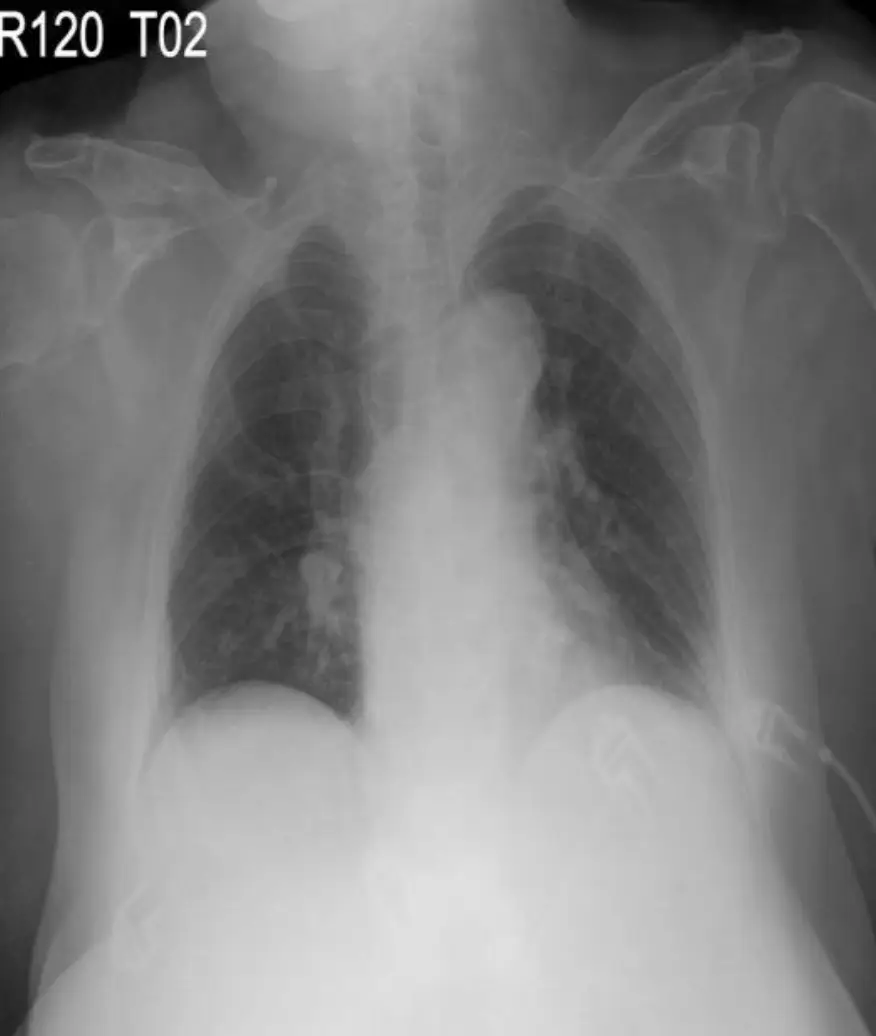

2. 胸部 X 光

• 心影大小正常,心臟輪廓無顯著擴大。

• 肺野清晰,未見肺充血或肺水腫徵象。

• 無主動脈撕裂或其他急性胸部病變影像。

正常的胸部 X 光排除急性心衰(如肺水腫)或主動脈夾層,以支持心肌梗塞的診斷與定位,而非其他胸悶原因。